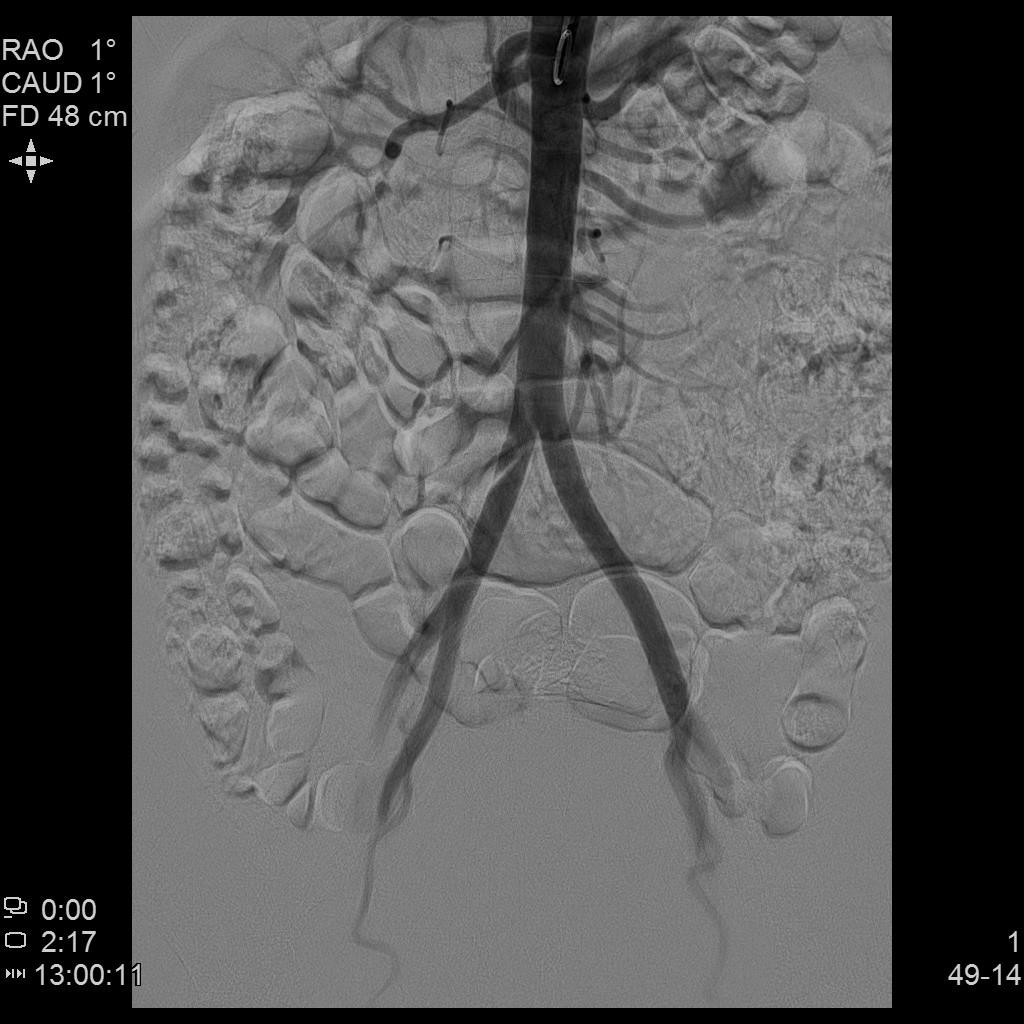

例3

中年患者,发现“子宫腺肌症”10年余,近5年痛经、月经量增多等症状明显加重,导致贫血,严重影响生活质量。

- 术前彩超、磁共振检查显示子宫明显增大,子宫前壁可见弥漫型子宫腺肌症病灶,合并粘膜下、肌壁间子宫肌瘤。

腹主动脉造影